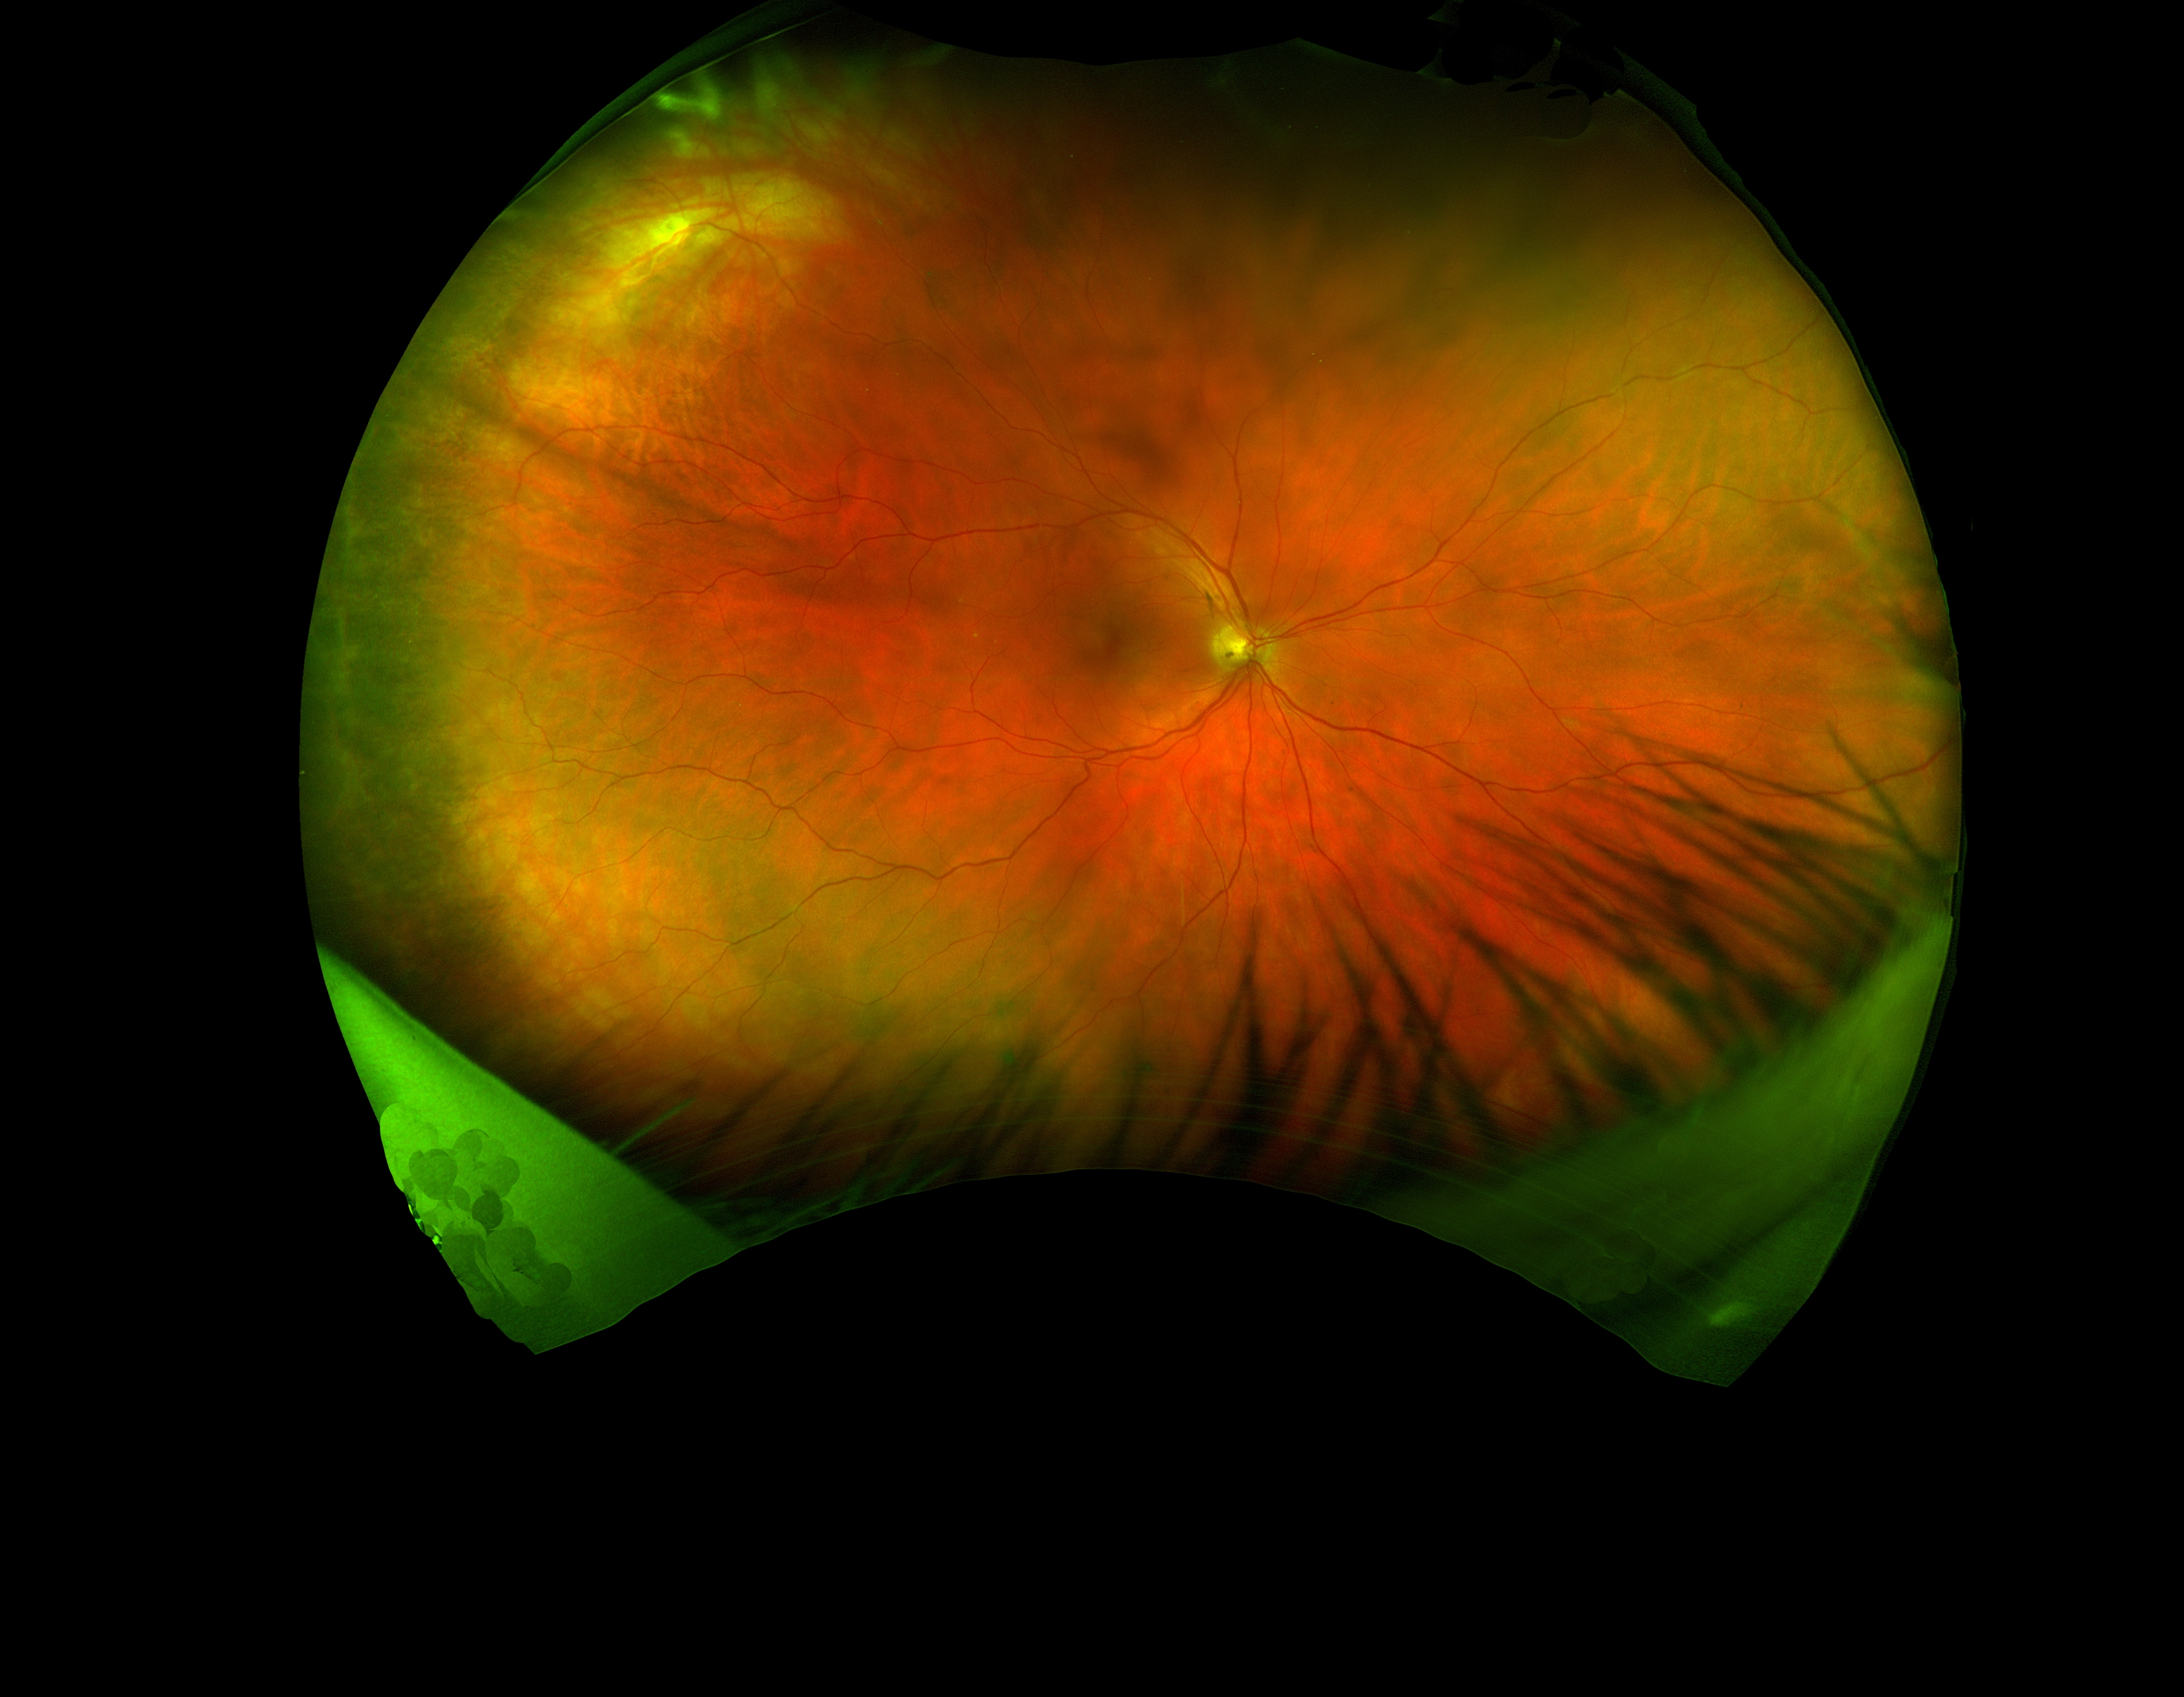

• The Retinal Tear